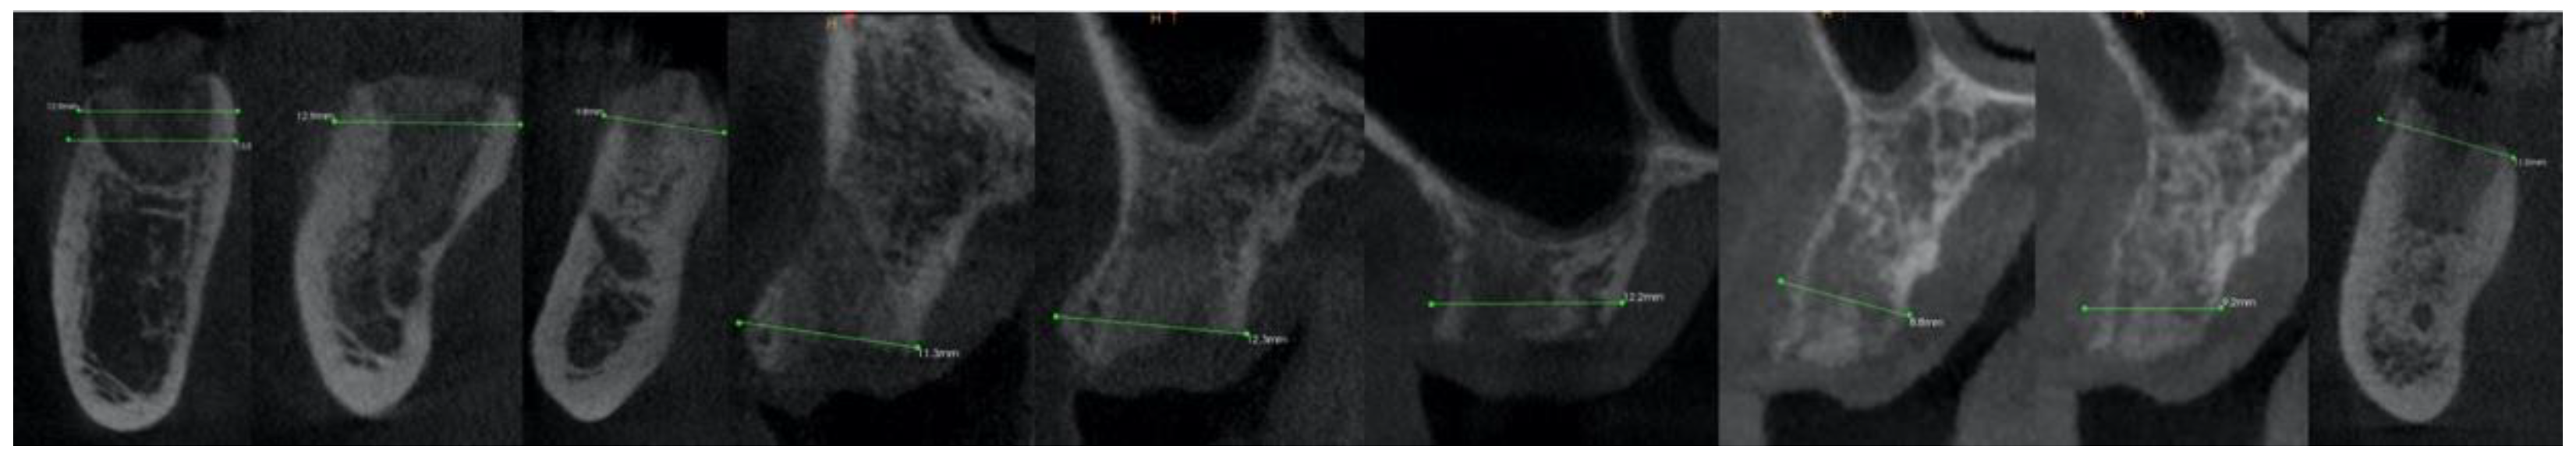

2.3. Radiographic Evaluation

| Case No. | Tooth No. | Initial Buccal Bone Thickness (mm) | Preoperative Bony Ridge Width (mm) | Postoperative Bony Ridge Width (mm) a | Δ |

|---|---|---|---|---|---|

| 1 | 47 | 0.80 | 12.50 | 12.90 | 0.40 |

| 2 | 37 | 0.80 | 12.00 | 12.90 | 0.90 |

| 3 | 34 | 0.70 | 9.20 | 9.80 | 0.60 |

| 4 b | 24 | 2.00 | 11.10 | 11.30 | 0.20 |

| 5 b | 25 | 2.00 | 12.00 | 12.30 | 0.30 |

| 6 | 16 | 1.20 | 11.90 | 12.20 | 0.30 |

| 7 c | 14 | 0.70 | 8.50 | 8.80 | 0.30 |

| 8 c | 15 | 0.70 | 8.80 | 9.20 | 0.40 |

| 9 | 36 | 1.70 | 10.70 | 11.00 | 0.30 |

| Mean RP | 1.18 | 10.74 | 11.16 | 0.41 | |

| SD | 0.57 | 1.54 | 1.57 | 0.21 | |